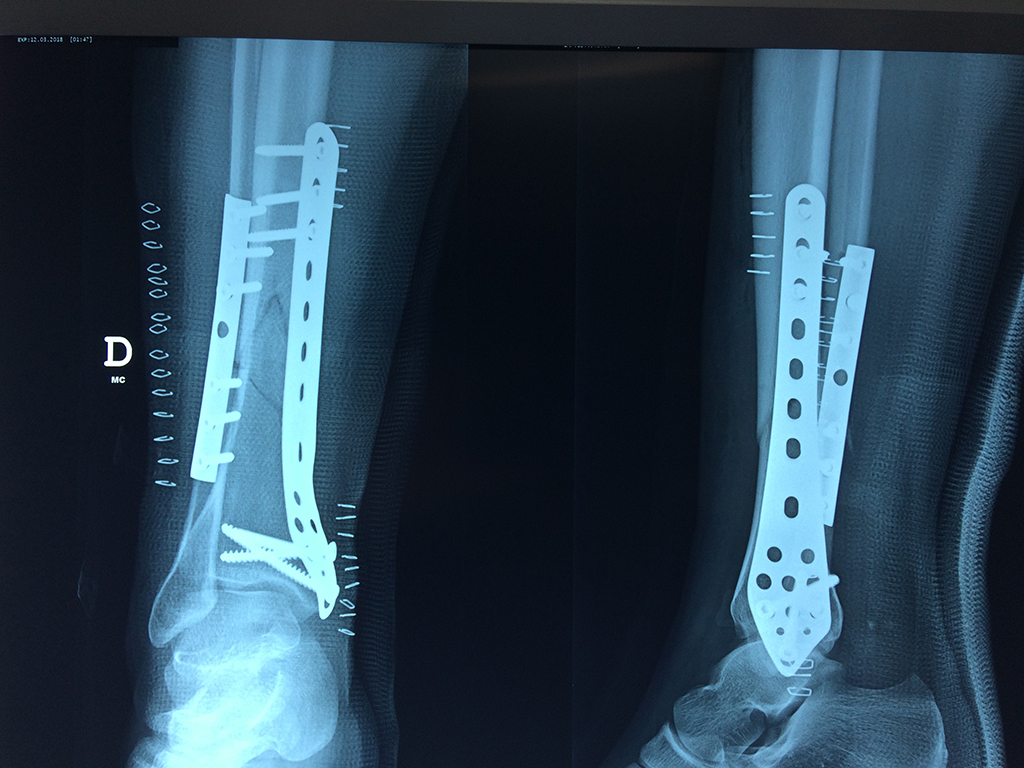

Fémur - Perone y Tibia

Aunque cada uno de estos huesos puede fracturarse por separado, normalmente la rotura es una lesión que se produce de forma conjunta

La mayor parte de las roturas implican a la parte proximal del hueso (parte del hueso próximo a la rodilla) o a la parte distal (parte del hueso cerca del tobillo).

Debido a la fina cobertura de piel que recubre la tibia y el peroné, las fracturas generalmente son abiertas, es decir, el hueso roto rasga la piel, atravesándola. Las fracturas de tibia y peroné generalmente se producen por un fuerte impacto o torsión.